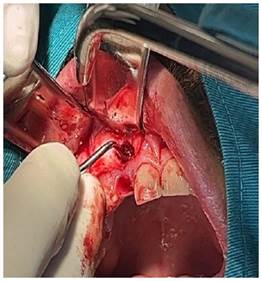

Obteniendo como diagnóstico presuntivo un quiste radicular asociado a la pieza 1.2; se le solicitó al paciente una biometría hemática, con todos los valores dentro de parámetros normales; se realizó el procedimiento quirúrgico de descompresión, por medio de una incisión lineal, el levantamiento del colgajo mucoperiostico y posterior osteotomía a nivel del ápice de la pieza 1.2, hasta descubrir la membrana del quiste (figura 3a), se extiende la ventana con un diámetro de aproximadamente 5 mm compatible con el diámetro del dren que colocaríamos, se realizó una incisión a nivel de la membrana del quiste y se drenó líquido seropurulento, se realiza el lavado mediante el orificio, con suero fisiológico y yodopovidona (Figura 3b).

Figura 3a Se observa ventana de 5 mm de diámetro que se realizó mediante osteotomía a nivel del ápice de la pieza 1.2; observamos la membrana del quiste.

Figura 3b Se retiro la membrana del quiste a nivel de la ventana ósea y se realizó el drenaje del líquido seropurulento, lavamos a través del orificio con suero fisiológico y yodopovidona.